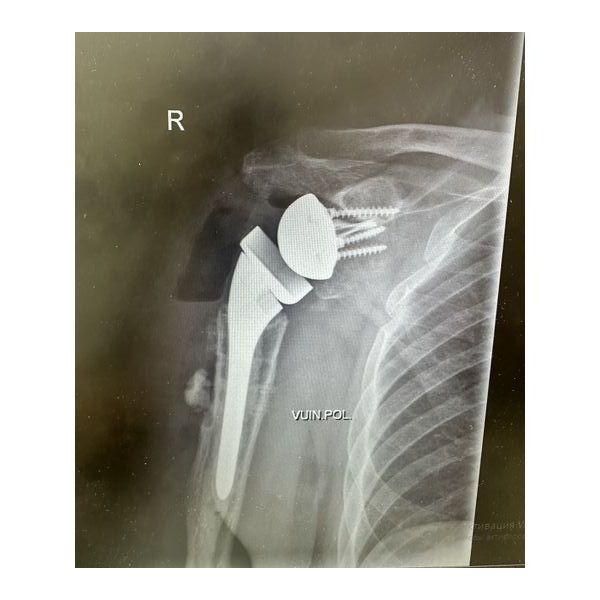

- удаления металлоконструкции в области верхнего конца плечевой кости;

- реверсивного эндопротезирования правого плечевого сустава (замены разрушенного сустава искусственным аналогом).

На следующий день после операции пациент отметил увеличение объёмов движений в области правого плечевого сустава.

Также отметил постепенный регресс болевого синдрома: сначала на фоне обезболивающей терапии, а в последующем — и без неё.